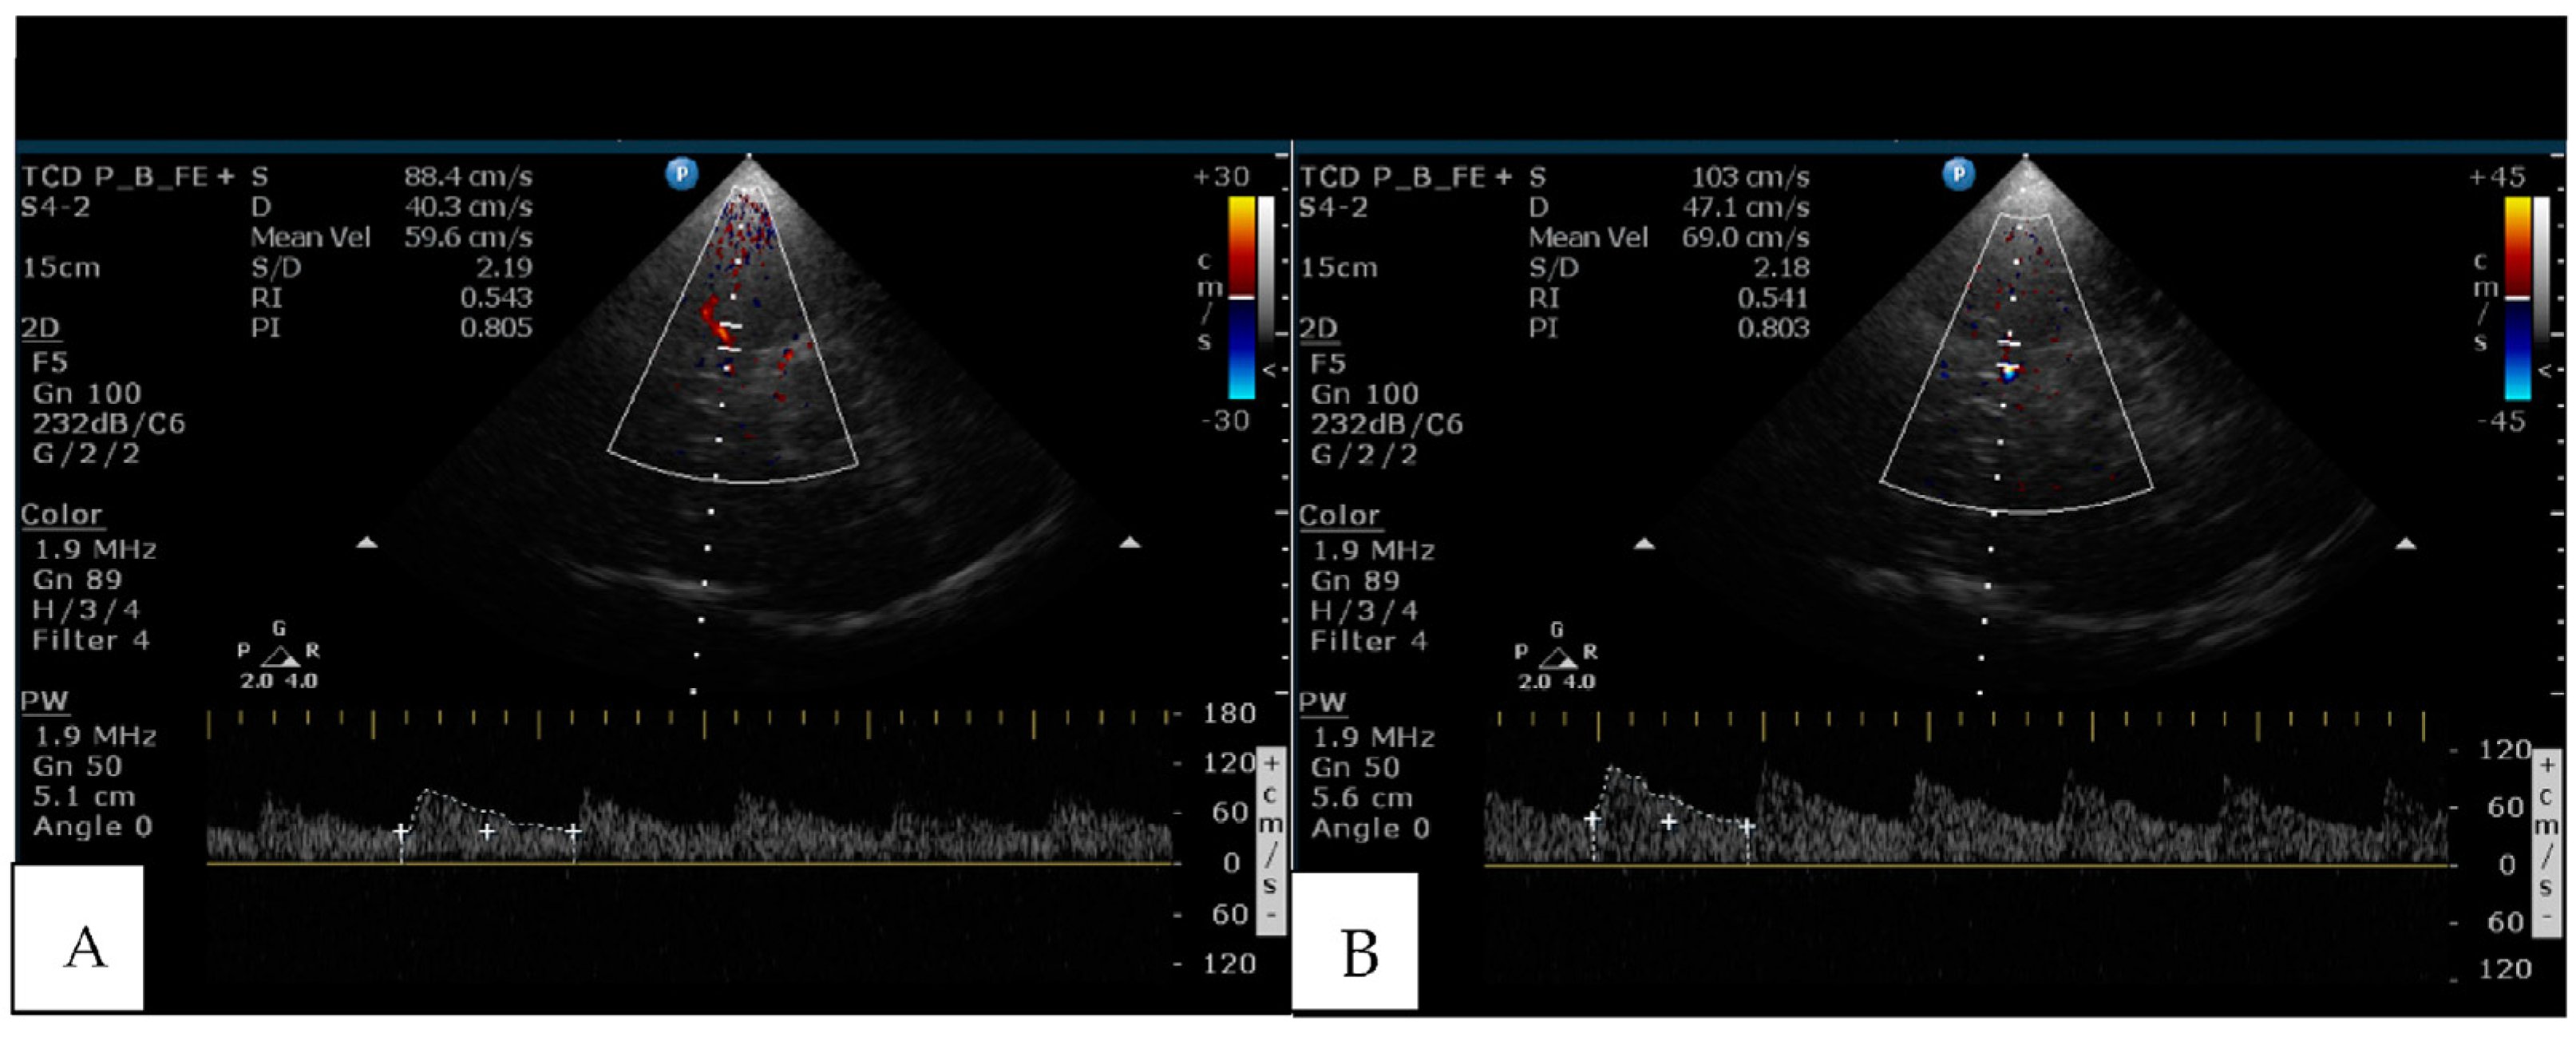

- Markus, H.S.; Harrison, M.J. Estimation of cerebrovascular reactivity using transcranial Doppler, including the use of breath-holding as the vasodilatory stimulus. Stroke 1992, 23, 668–673. [Google Scholar] [CrossRef]